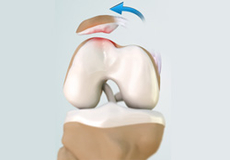

Movement of the bones causes friction between the articulating surfaces. To reduce this friction, all articulating surfaces involved in the movement are covered with a white, shiny, slippery layer called articular cartilage. The articulating surface of the femoral condyles, tibial plateaus and the back of the patella are covered with this cartilage. The cartilage provides a smooth surface that facilitates easy movement.

To further reduce friction between the articulating surfaces of the bones, the knee joint is lined by a synovial membrane that produces a thick clear fluid called synovial fluid. This fluid lubricates and nourishes the cartilage and bones inside the joint capsule.

Within the knee joint, between the femur and tibia, are two C-shaped cartilaginous structures called menisci. Menisci function to provide stability to the knee by spreading the weight of the upper body across the whole surface of the tibial plateau. The menisci help in load-bearing i.e. it prevents the weight from concentrating onto a small area, which could damage the articular cartilage. The menisci also act as a cushion between the femur and tibia by absorbing the shock produced by activities such as walking, running and jumping.